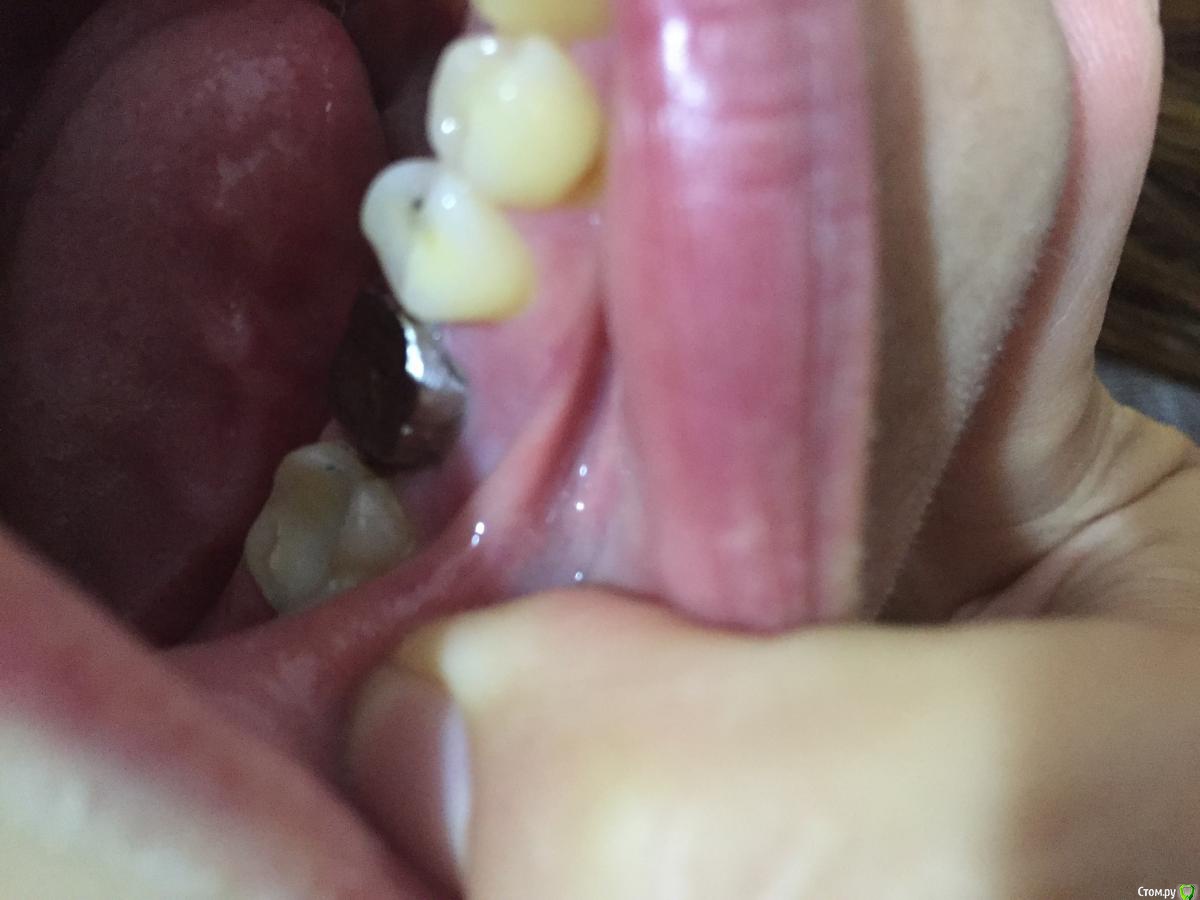

Мария Сп Опубликовано 28 сентября, 2018 Поделиться Опубликовано 28 сентября, 2018 (изменено) Здравствуйте, уважаемые доктора!Просьба помочь. Зуб треснул, доктор сказал нужно устанавливать металлокерамическую коронку. Взяли слепок. Через 2 недели установили культю, т.к. от зуба остался только корень и металлическую основу под керамическую коронку (заранее извиняюсь, не знаю как правильно называется металлическая основа).После установки данной металлической основы доктор сказал, что у меня зуб широкий и плоский и, что вероятнее всего керамика не покроет весь металл и будет видно металл с внутренней стороны и верхней (жевательной), т.к. осталось слишком мало места между нижней коронкой и верхним зубом. Металлическую основу доктор подточил на сколько мог, сказал, что больше не может. Также стал точить верхний зуб, но мне стало больно. Подскажите, пжл, неужели действительно в моем случае нужно, чтобы металлическая основа была настолько высокой, что нет места керамике?Можно ли это было предусмотреть и предупредить меня еще до изготовления культи и металлической основы?Можно ли переделать данную конструкцию, предполагаю, что данная металлическая основа вылита изначально сильно большой?Также доктор не устанавливал временную коронку, только металлическую основу, сделал слепок и через 2 недели ставить керамическую коронку?И могу ли я, если меня не устроит результат - сильно будет виден металл, попросить переделывать всю коронку не доплачивая?Фото прилагаю.Заранее спасибо. Изменено 28 сентября, 2018 пользователем Мария Сп Ссылка на комментарий

Мария Сп Опубликовано 30 сентября, 2018 Автор Поделиться Опубликовано 30 сентября, 2018 Фото с сомкнутыми зубами направляю. Ссылка на комментарий